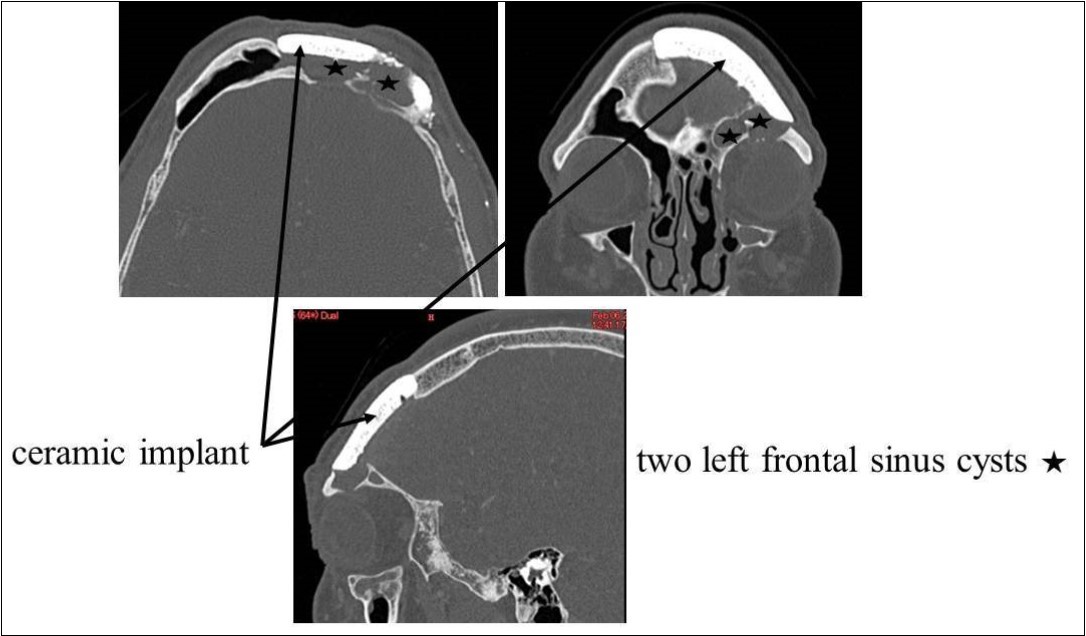

Recurrent frontal sinusitis was suspected, and the patient was referred to our department for evaluation on February 14, 2007. On initial evaluation, the left upper eyelid swelling was resolved; however, paranasal sinus computed tomography (CT) showed two left frontal sinus cysts (Figure 1). The patient had a history of hypertension that was well-controlled on oral medications. No other major disorders were present, including diabetes or heart disease.

Figure 1.CT of the paranasal sinuses showed two left frontal sinus cysts. Black arrows: ceramic implant. Black stars: two left frontal sinus cysts